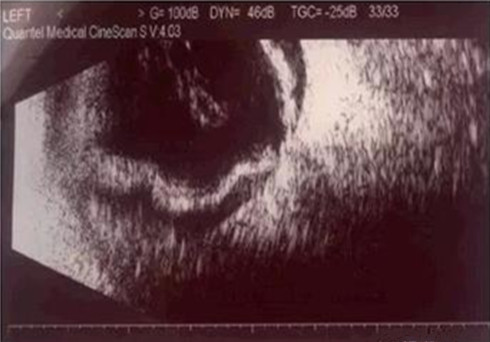

术后左眼视力:1尺光感至眼前手动,眼压:6~8 mmHg,前房积血,玻璃体腔凝血块,眼底窥不清。术后第3天复查眼部B超,显示左眼玻璃体腔浓密积血,窄漏斗状视网膜脱离,部分出血性脉络膜脱离(图3)。